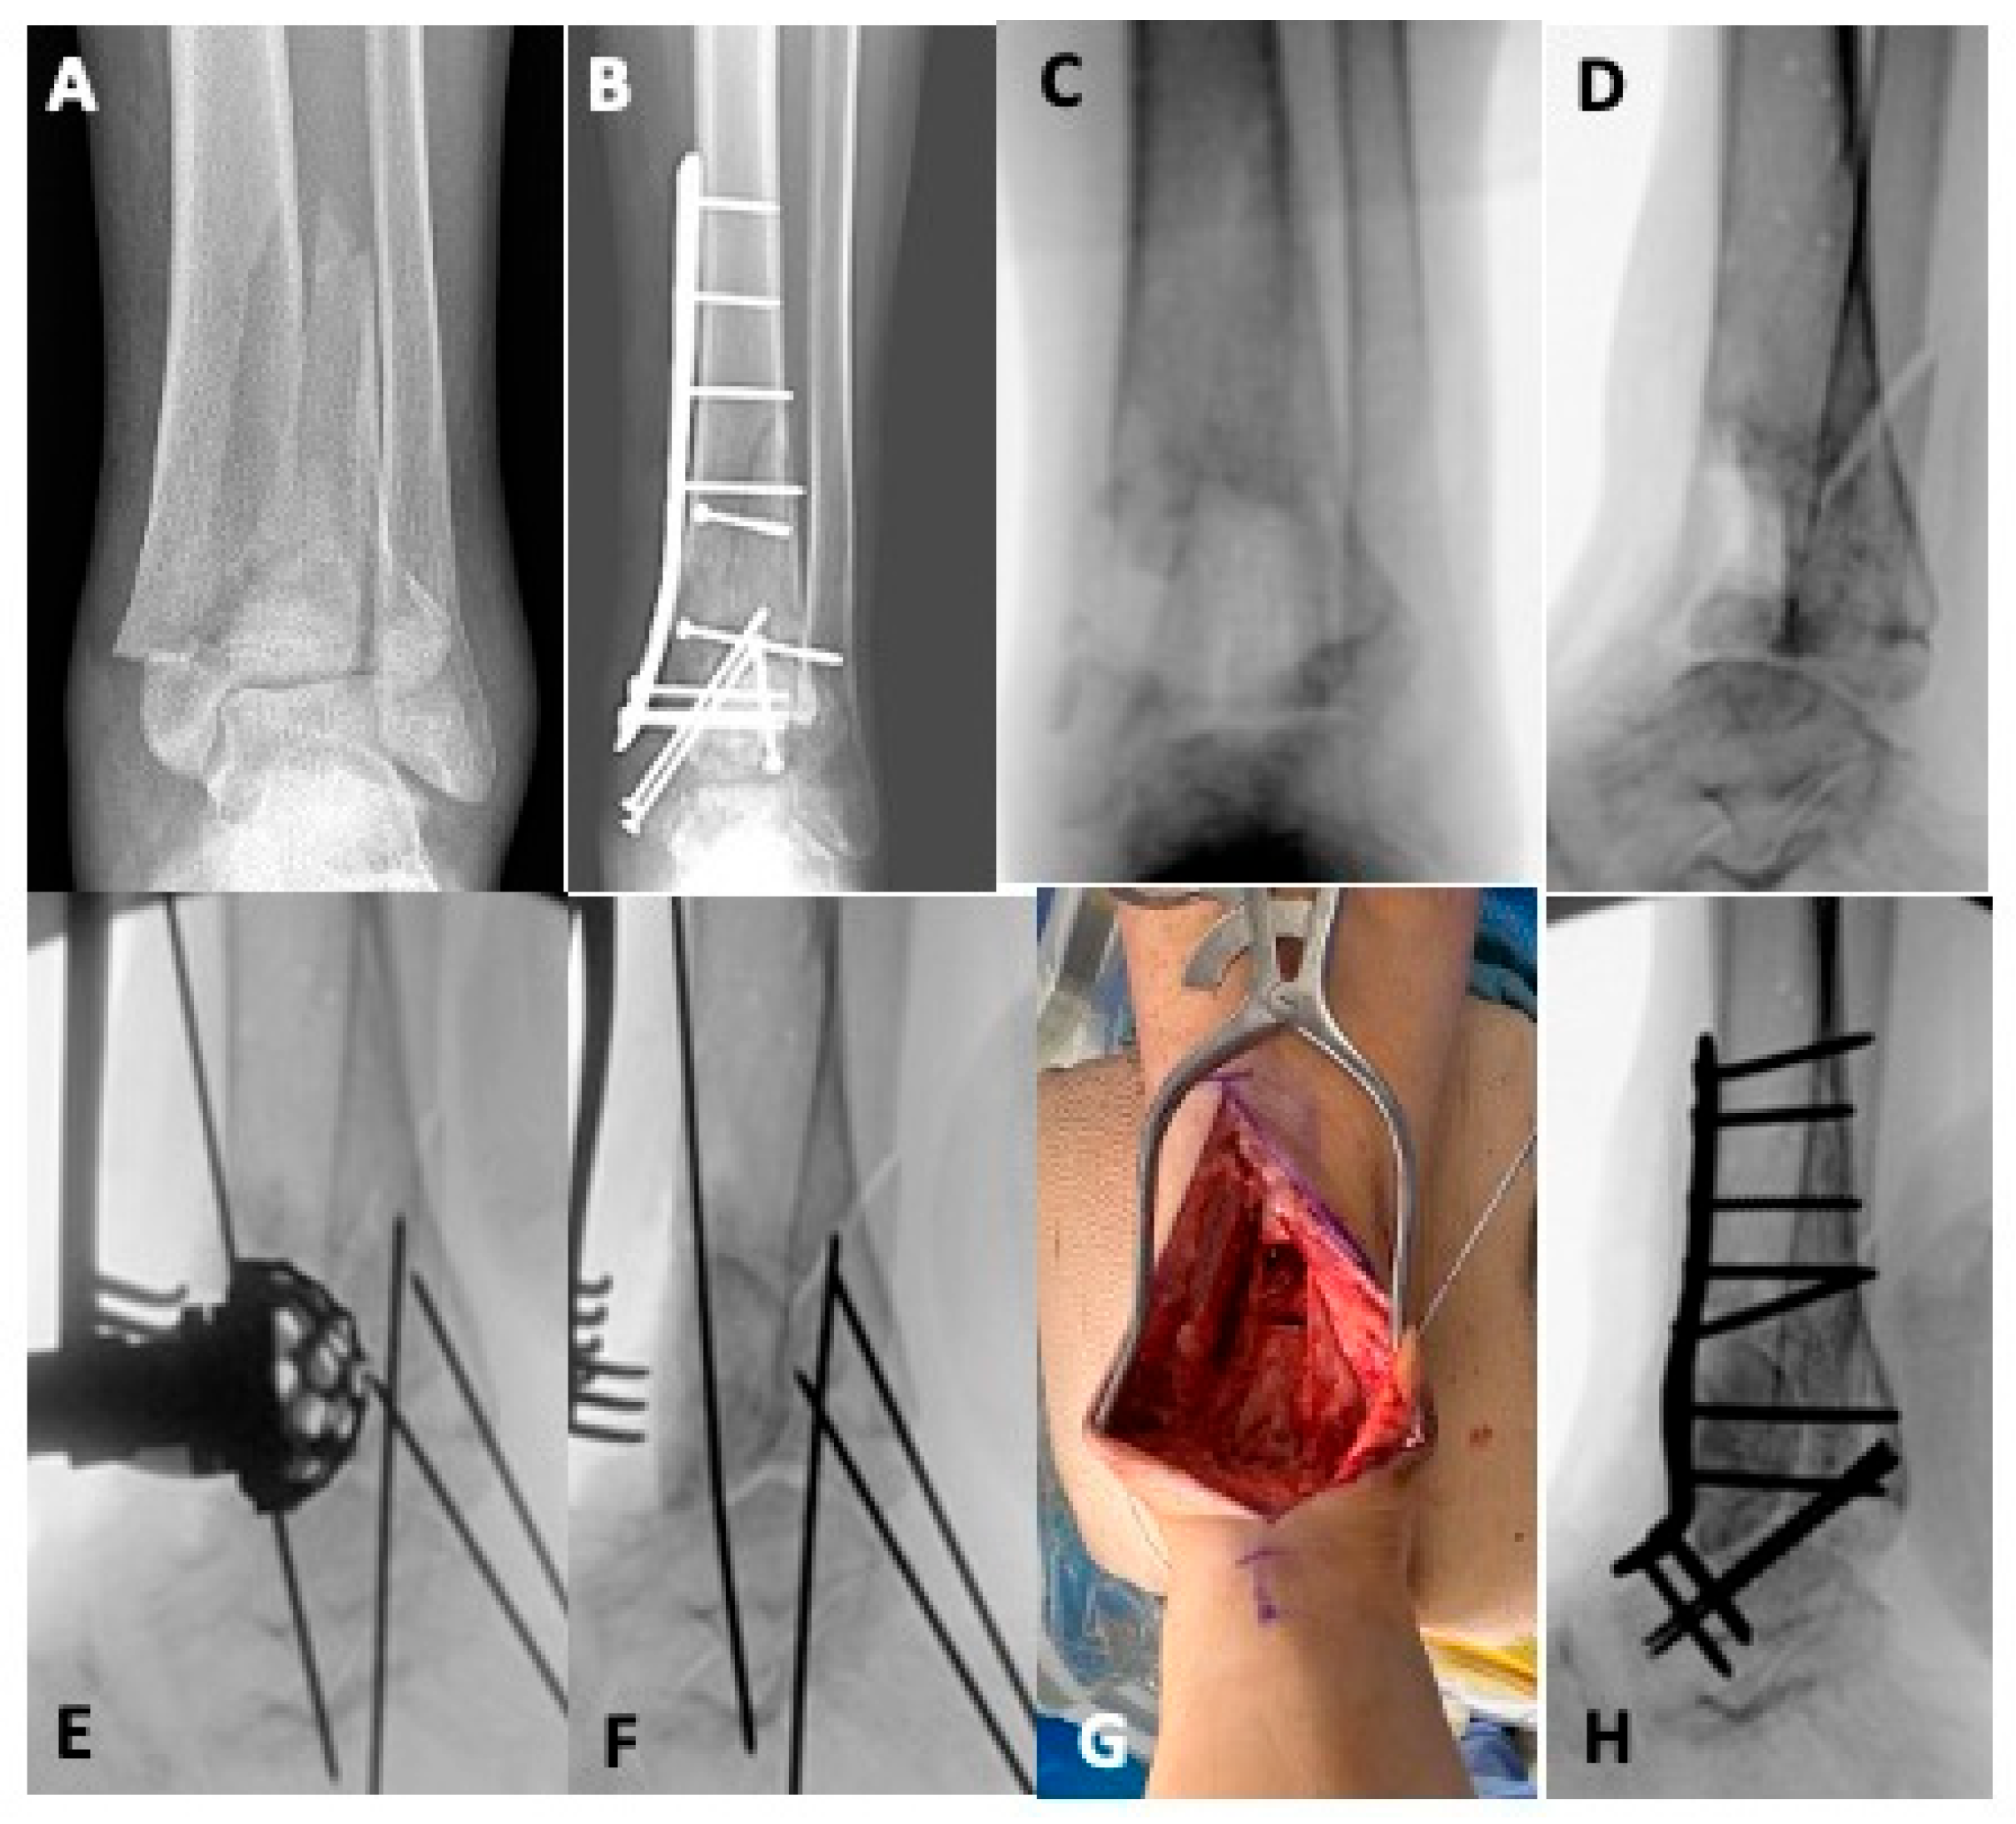

5.1. Revision Operative Fixation

5.2. Joint-Sacrificing Reconstruction

5.2.2. Tibiotalar Arthrodesis